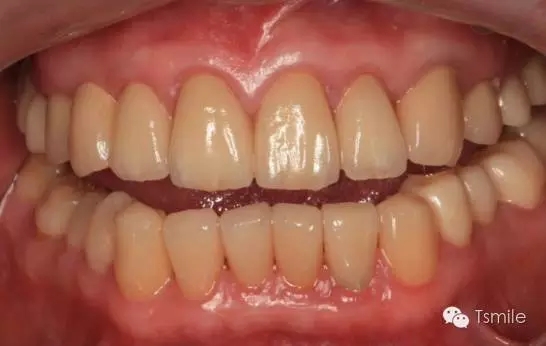

前兩個(gè)美學(xué)分析和美學(xué)表達(dá)過程已經(jīng)確定了患者滿意的最終的美學(xué)修復(fù)設(shè)計(jì),也就是已經(jīng)確定了最終修復(fù)體的形態(tài)、大小、排列、牙齦曲線等各種美學(xué)參數(shù),美學(xué)實(shí)現(xiàn)就是復(fù)制前面已經(jīng)確定的美學(xué)設(shè)計(jì)的過程,包括牙體預(yù)備、印模制取、修復(fù)體制作、修復(fù)體試戴粘接等過程。

例如面對(duì)一個(gè)牙列重度磨耗的美學(xué)修復(fù)患者,我們首先根據(jù)患者主訴和美學(xué)檢查形成美學(xué)設(shè)計(jì),然后通過數(shù)碼圖像表達(dá)美學(xué)設(shè)計(jì)思想,制作診斷蠟型,口內(nèi)制作診斷飾面,更加真實(shí)地表達(dá)美學(xué)設(shè)計(jì)。根據(jù)患者的要求和口內(nèi)試戴情況調(diào)改診斷飾面,最終確定美學(xué)修復(fù)設(shè)計(jì),即最終修復(fù)體的各種美學(xué)參數(shù)。接下來就是美學(xué)實(shí)現(xiàn)過程,在診斷飾面上進(jìn)行精確地牙體預(yù)備,制取印模和工作模型,技師按照最終診斷飾面的形態(tài)、大小和排列制作最終美學(xué)修復(fù)體,最后完成修復(fù)體粘接。

圖6:最終修復(fù)體完成